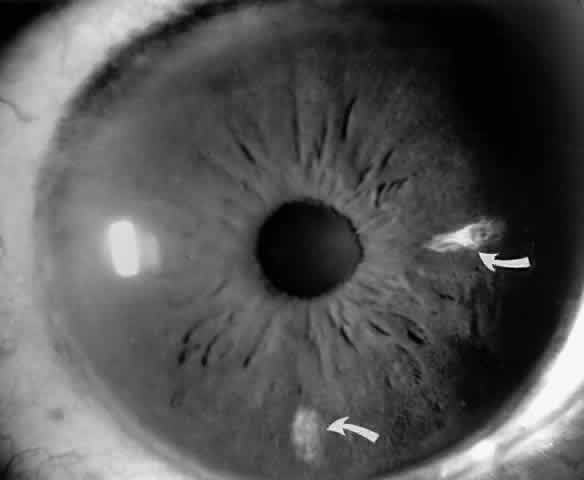

Iris Atrophy and Neovascularization

Occlusions of the iris vessels can result in atrophy, and patients may present with asymptomatic white patches of the iris.50,51 The area of atrophy may be extensive (Fig. 2) and may be associated with pupillary irregularity. Iris neovascularization may develop in eyes with chronic retinal detachment or major arteriole occlusions and can in rare cases cause a secondary neovascular glaucoma.52